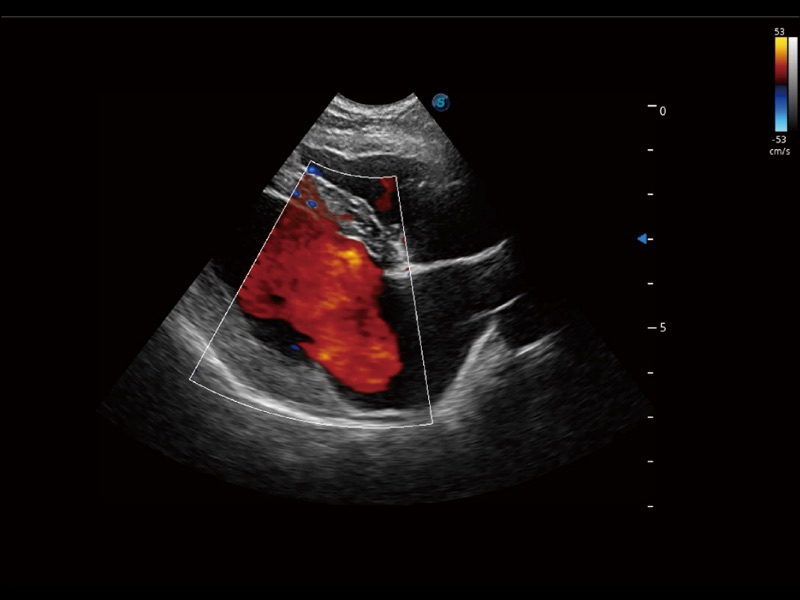

采用红、橙、黄、绿、青、蓝、紫这七种肉眼最为敏感的色彩,直观地显示组织内血流灌注的时间先后信息,更精准捕捉血流灌注走行细节。

能够基于左心室壁追踪和辛普森法,自动计算射血分数,支持多个可移动点描迹,与手动测量相比,极大节省了动物医生的时间和精力。

通过创新的 Matrix E自适应滤波器和超长时间域算法,极大提升超低速微细血流的检出能力,同时更精准地滤除软组织和噪声信号,为兽用医生提供以往无法通过常规血流获得的疾病诊断信息。

实时用颜色表示心肌组织运动,观察和定量组织的运动情况,对快速检测与评估心肌的灌注和活性、电传导及心肌收缩和舒张功能等均能提供重要的诊断信息。